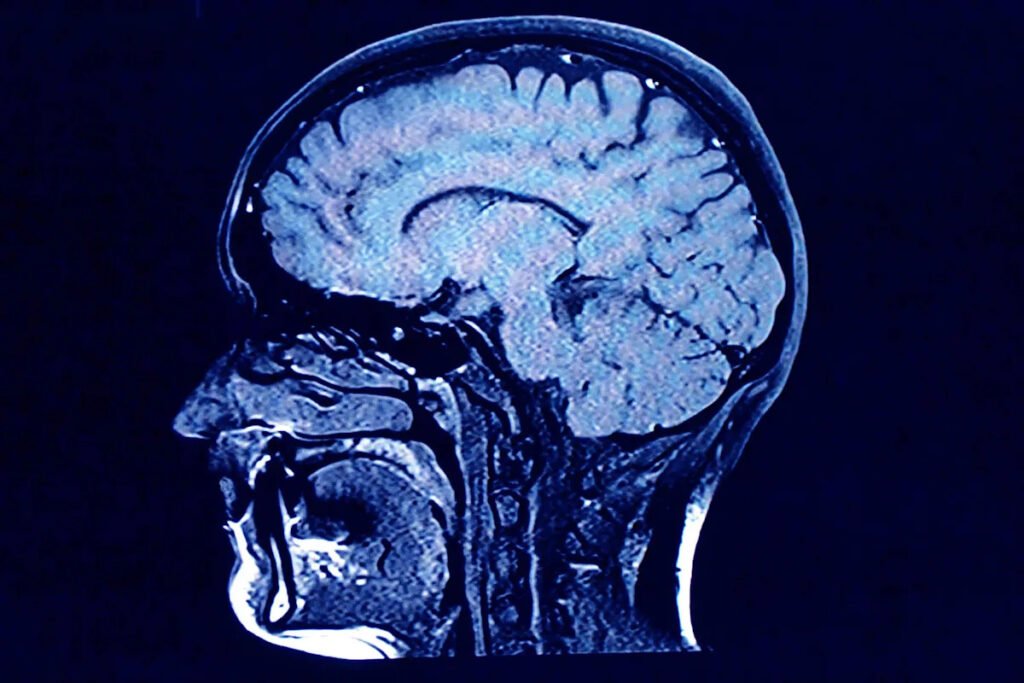

As we age, the human brain rewires itself.

The process happens in distinct phases, or “epochs,” according to new research, as the structure of our neural networks changes and our brains reconfigure how we think and process information.

For their research, Mousley and her colleagues analyzed MRI diffusion scans — which are essentially images of how water molecules move within the brain — from about 3,800 people from newborns to age 90. The goal was to map the neural connections across the average person’s brain at different stages in life.

In the brain, the bundles of nerve fibers that transfer signals are encapsulated in fatty tissue called myelin. Think of it like wiring or plumbing. Water molecules diffused in the brain tend to move in the direction of these fibers, rather than across them, meaning researchers can infer where the neural pathways are located.

Based on the MRI scans, the new study maps the neural network of an average person across a lifespan, determining where connections are strengthening or weakening. The five “epochs” it describes are based on the neural connections the researchers observed.